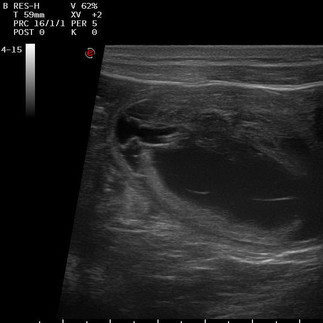

Der lang ersehnte Termin zum Ultraschall stand an.

Am 08.12.2025 waren wir in Dortmund bei Fr. Dr. Möhrke zur Trächtigkeitsuntersuchung.

Frau Dr. Möhrke bestätigte was wir durch Lana's Verhalten (mäkelte plötzlich am Futter und ist sehr verschmust) schon vermuteten.

Es konnten 10-11 intakte Fruchtanlagen (evtl. mehr) gezählt werden, was natürlich wir so auch nicht erwartet hätten. Allerdings kann natürlich noch einiges passieren, deshalb ist das nur eine grobe Richtung.